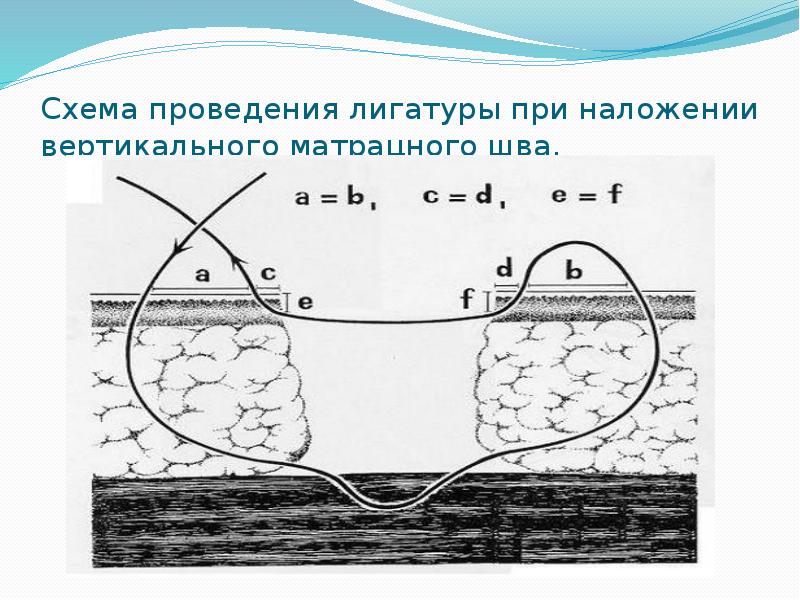

- 31. Схема проведения лигатуры при наложении вертикального матрацного шва.